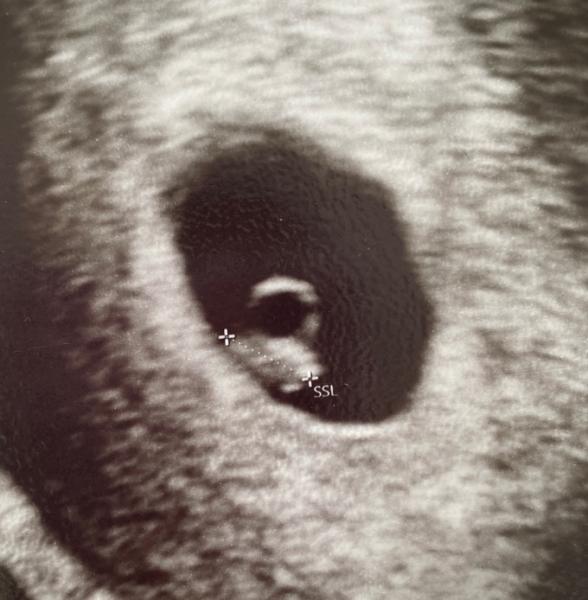

Heute bei 6+1 den ersten Termin gehabt.

Sieht alles super aus und das Herz hat auch schon fleißig geschlagen